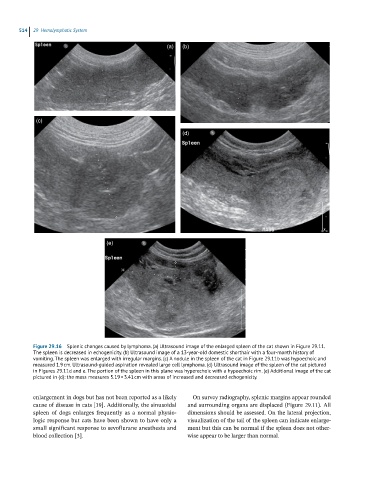

Figure 29.16 Splenic changes caused by lymphoma. (a) Ultrasound image of the enlarged spleen of the cat shown in Figure 29.11.

The spleen is decreased in echogenicity. (b) Ultrasound image of a 13-year-old domestic shorthair with a four-month history of

vomiting. The spleen was enlarged with irregular margins. (c) A nodule in the spleen of the cat in Figure 29.11b was hypoechoic and

measured 1.9 cm. Ultrasound-guided aspiration revealed large cell lymphoma. (d) Ultrasound image of the spleen of the cat pictured

in Figures 29.11d and e. The portion of the spleen in this plane was hyperechoic with a hypoechoic rim. (e) Additional image of the cat

pictured in (d): the mass measures 5.19 × 3.41 cm with areas of increased and decreased echogenicity.